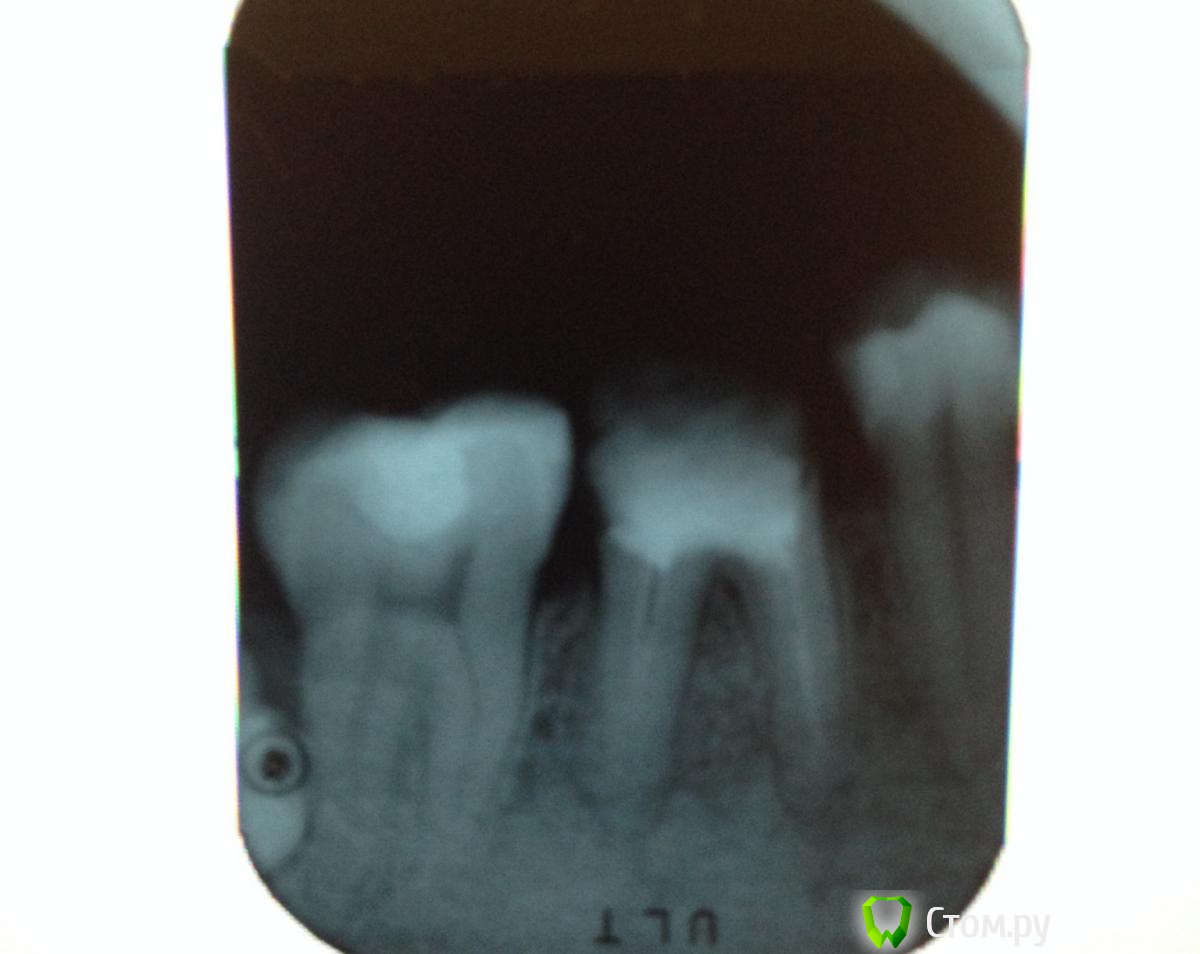

Yana5 Опубликовано 4 января, 2014 Поделиться Опубликовано 4 января, 2014 Здравствуйте! 2) Посоветуйте, пожалуйста, что можно сделать с нижними 6- ками в моем случае? Под коронкой на правой 6-ке началось воспаление, коронку сняли, врач почистил каналы, сейчас она выглядит так: Мне бы хотелось поставить туда коронку, как вы считаете, это возможно? Если да, то какую? 1) Прокомментируйте, пожалуйста, мой панорамный снимок. Ссылка на комментарий

IvanK Опубликовано 4 января, 2014 Поделиться Опубликовано 4 января, 2014 Здравствуйте. 6 ки перелечить, далее под коронки. 8 ки удалять 14. 15. 26 тоже перелечить и под коронки. 2 Ссылка на комментарий

red_butler Опубликовано 5 января, 2014 Поделиться Опубликовано 5 января, 2014 Большое спасибо за быстрый ответ!А 14. 15. 26 - перелечить, потому, что они запломбированы плохо?Не выполнена полноценная механическая обработка и запломбированы не до конца, как следствие хронические воспалительные очаги. Ищите стоматолога - эндодонтиста, работающего с коффердамом и в идеале с оптикой 1 Ссылка на комментарий